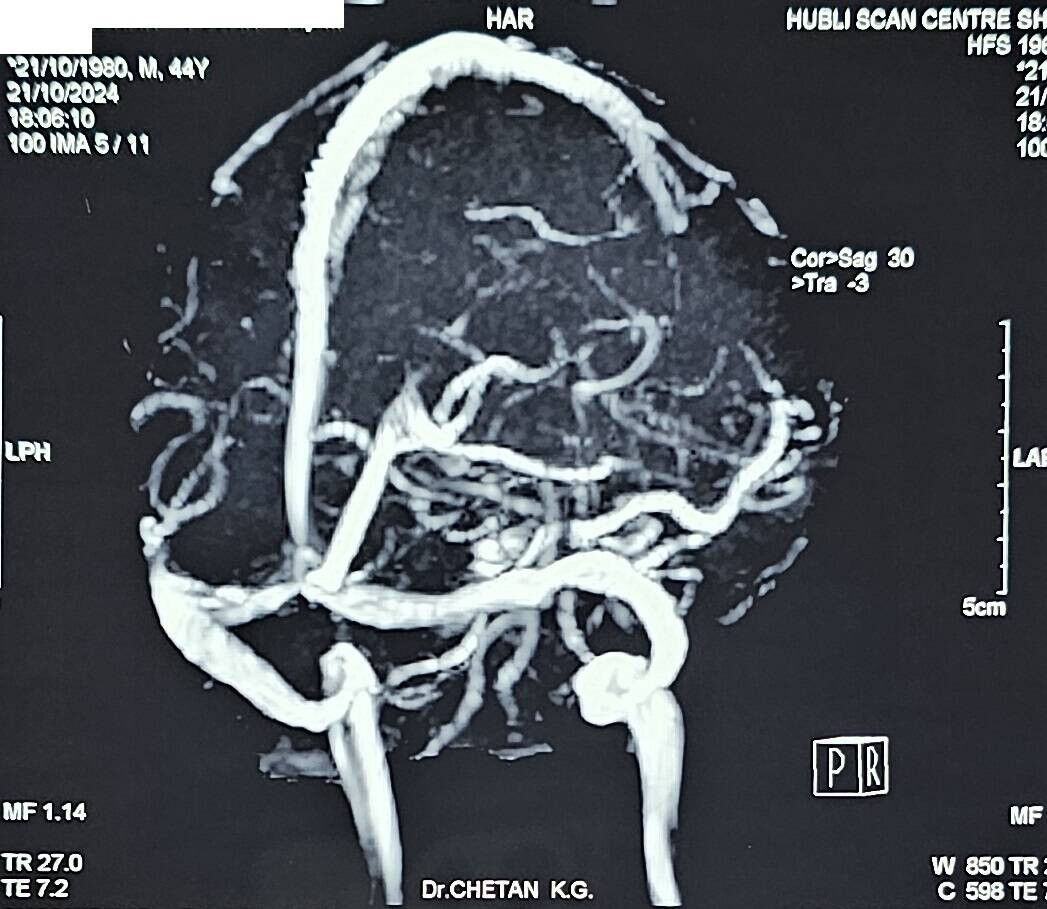

#10 - Persistent giddiness in young lady - How imaging played an important role in clinching the diagnosis - A case report by Dr. Chetan K. Ganteppanavar

A 34-year-old female, with giddiness and mild headache for approximately 2 years. She was a mother of two kids, had uneventful pregnancies, and had no other co-morbid diseases. She had consulted for the above complaints for 2 years, and treated by local practitioners, and the ENT evaluations were normal. Multiple physician and neurologist consultations were done.